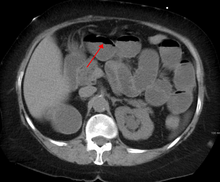

A small bowel obstruction as seen on CT

The main diagnostic tools are blood tests, X-rays of the abdomen, CT scanning, and/or ultrasound. If a mass is identified, biopsy may determine the nature of the mass.

Radiological signs of bowel obstruction include bowel distension and the presence of multiple (more than six) gas-fluid levels on supine and erect abdominal radiographs.

Contrast enema or small bowel series or CT scan can be used to define the level of obstruction, whether the obstruction is partial or complete, and to help define the cause of the obstruction.